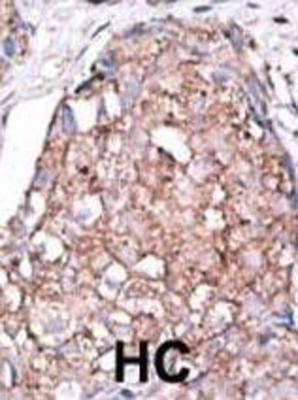

Applikationen WB, IHC, ELISA

Sialic Acid Binding Ig Like Lectin 7 (SIGLEC7)